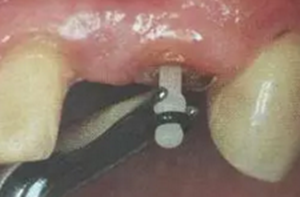

(超聲去除根管殘留物)

通常此時(shí)以超聲潔牙機(jī)更換較細(xì)工作尖進(jìn)入根管(根管消毒沖洗液配合清潔工作后面會(huì)提到),徹底去除樁道根管壁上的附著殘留物,效果明顯。再配合X線片、根管顯微鏡輔助檢查清理的情況下更佳。